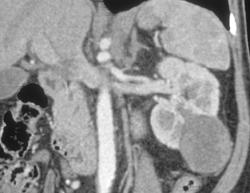

Normal 3D of Renal Arteries